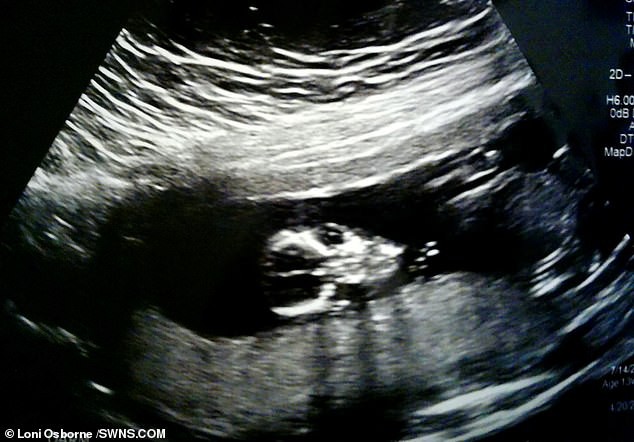

Ở tuần 20 của thai kỳ, khi đi siêu âm nhân viên y tế cho biết rằng họ không thể đo chính xác kích thước chân tay bé Theo. Một bác sĩ sản sau đó đã đề nghị Loni siêu âm thêm, đó chính là lúc Theo được chẩn đoán mắc chứng xương giòn, dễ gãy, đây là căn bệnh do di truyền thường do sự thiếu hụt mô liên kết và collagen gây nên. Nó có thể tác động tới mắt, chiều cao, răng, xương và việc hít thở. Triệu chứng có thể rất khác nhau tuỳ theo từng bệnh nhân.

Bác sĩ không thể đo chính xác kích thước tay chân của bé Theo